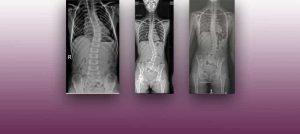

L’Institut Chiari de Barcelona és un centre neuroquirúrgic d’alta especialització dedicat al diagnòstic i tractament de malalties relacionades amb la columna vertebral i el cervell, centrat en el concepte clínic de la malaltia del Filum terminale. Entre les patologies que tracta s’inclouen: